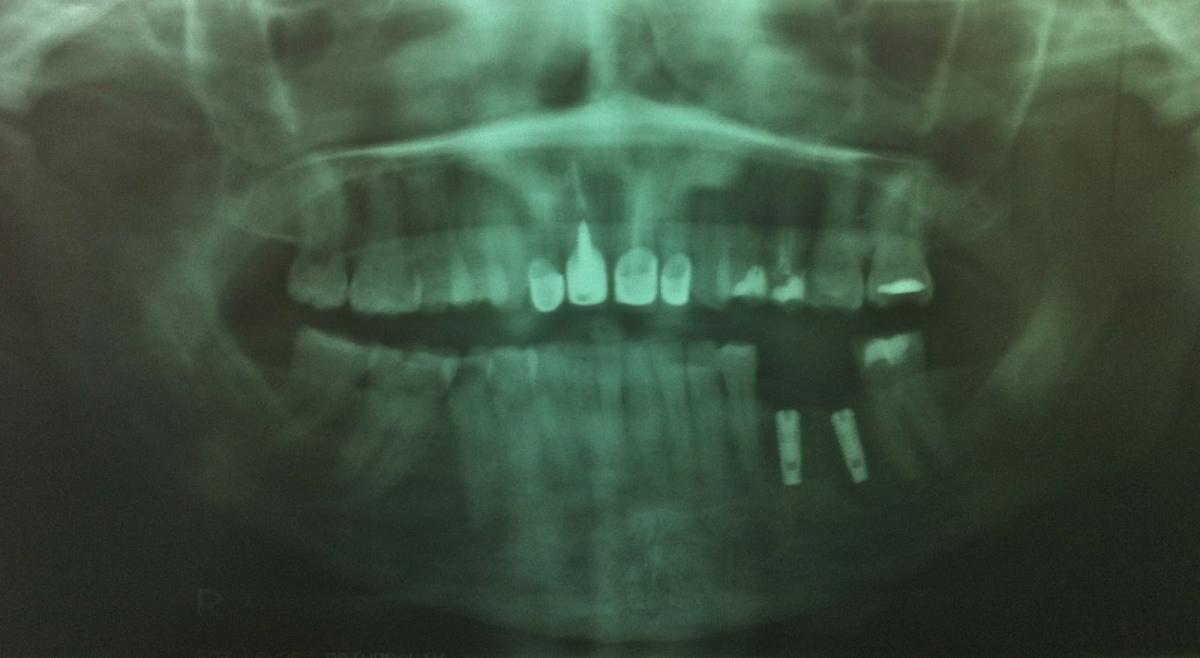

Panoramic xray - Cebu

The Panoramic x-ray, is a two-dimensional (2-D) dental x-ray examination that captures all completely the mouth in a single image this are the following the teeth, upper and lower jaws, surrounding structures and tissues.